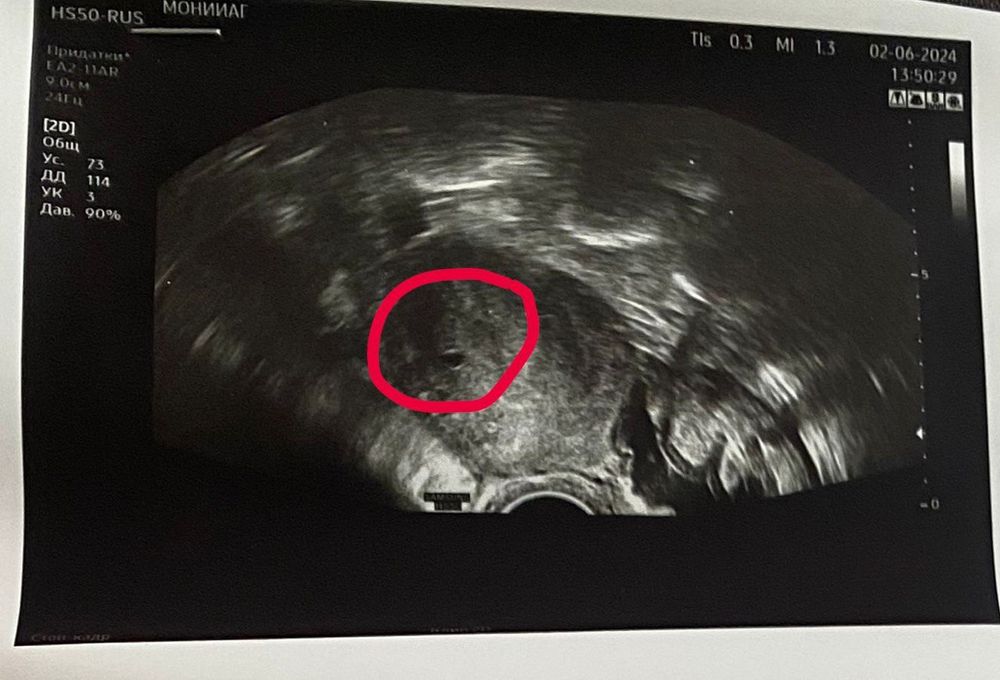

А я все жду чуда 😍 в Склифе после лапароскопии 😊 У меня разрыв кисты в правом яичнике. Редуцировали (удалили) часть яичника, но сохранили 🙏 Внематочную не нашли. Дали 2 таблетки дюфастона на ночь, на утро назначили хгч) Ре на узи сегодня видела что-то вроде маленького плодного яйца, которое соответствует хгч 800, но у меня было 3488. Остается понять: беременность развивающаяся или неразвивающаяся. Посмотрите: ведь на фото видно яйцо, хоть и маленькое?)

Виктория Львовская, спасибо, пока еще высокий хгч, на фото видно маленькое плодное яйцо, надежда есть 🤞🙏❤️